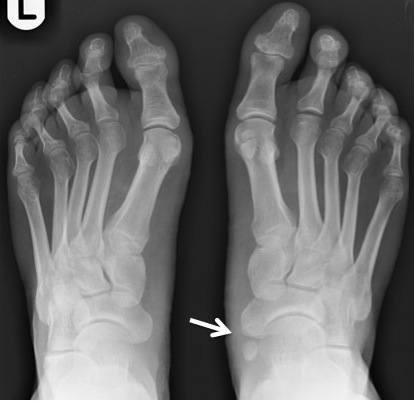

부주상골 증후군은 눈으로도 진단이 되기도 합니다. 발목 안쪽에 뼈가 튀어나와있습니다. 이 증후군은 스포츠 선수에게 많이 나타나는 발 손상입니다. 그리고 많은 분이 이 증상으로 군대를 면제받는지에 대해서 궁금해합니다.

이렇게 튀어나와 있는 뼈는 발 중간의 발등이나 아치에 위치한 작은 뼈 중 하나입니다. 나비 뼈라 불리며 여분의 뼈 중 하나이기도 합니다.

성장 과정에서 나비 뼈는 하나의 단단한 뼈로 융합되지 않고 섬유조직과 연골로 연결됩니다. 이는 정상적인 뼈가 아니며 보통 사람에게는 없는 뼈입니다. 보통 무증상이기 때문에 이 뼈의 존재 자체도 모를 수 있습니다.

만약 이 뼈로 인해 통증이 나타나면 문제가 됩니다. 나비 뼈는 돌출이 되기 때문에 쉽게 분간이 됩니다. 또한 돌출된 뼈로 인해 옷이나 다른 것에 접촉이 생기면 통증이 발생할 수도 있습니다. 이런 통증이 있는 상태를 부주상골 증후군이라고 합니다.

• 발 안쪽의 아치 바로 위 가시적 뼈 돌출